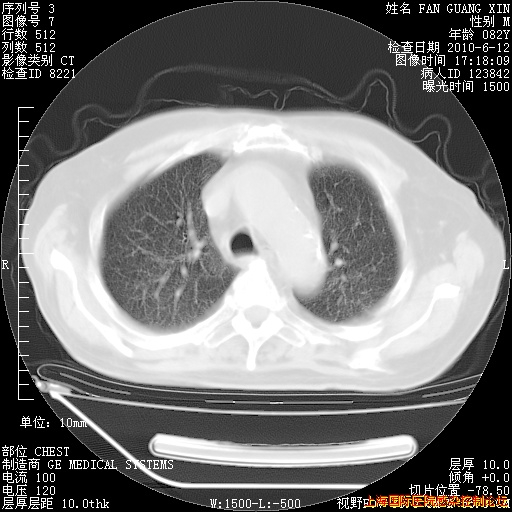

6月12日肺窗

整整相隔30天的肺部CT好像有所好转啊。甲强龙减量第3天,需要观察体温。